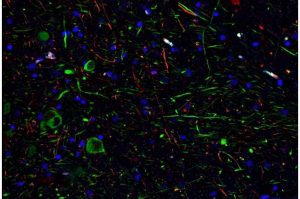

SARS-CoV-2 può infettare i neuroni della dopamina causando senescenza

SARS-CoV-2-Immagine:il tessuto colorato del mesencefalo di un paziente COVID-19 mostra il DNA nei nuclei delle cellule (blu), nei neuroni della…